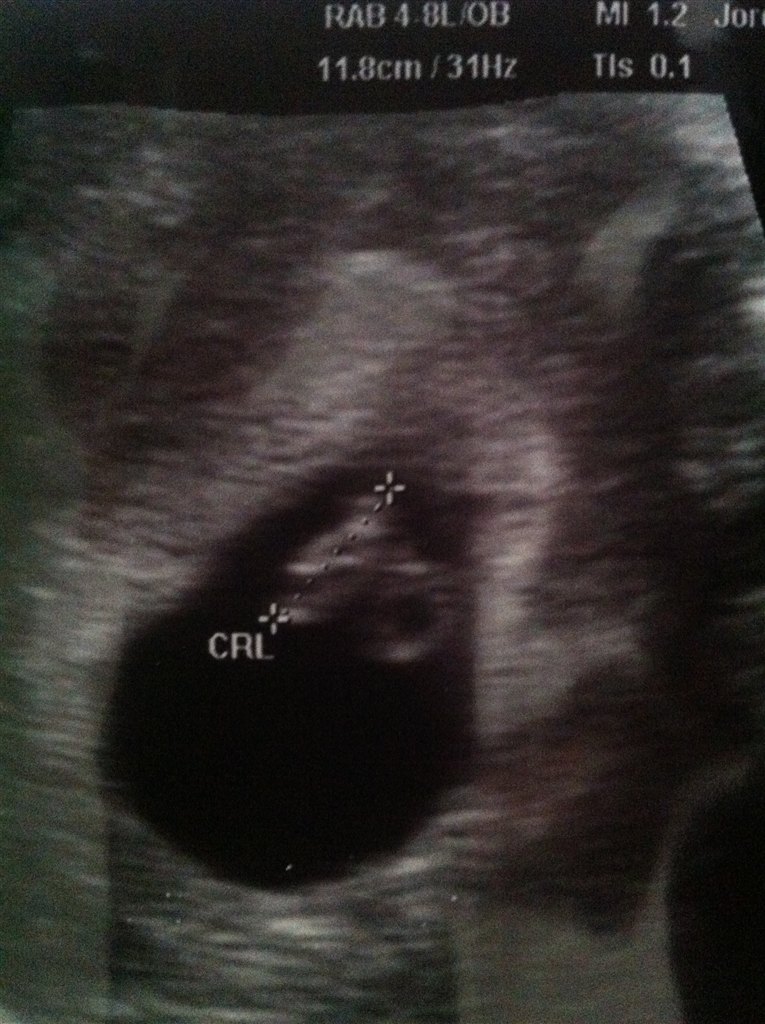

Tillykke søde, hvor er det bare skønt, og risikoen for SA er super lav, nu hvor du har set og hørt hjertet

Jeg har ikke engang været til 1 lægebesøg endnu.. Valgte bare at blive scannet da jeg ikke vidste hvor langt henne jeg var..

Men NØJ det var fantastisk at høre hjertelyden..